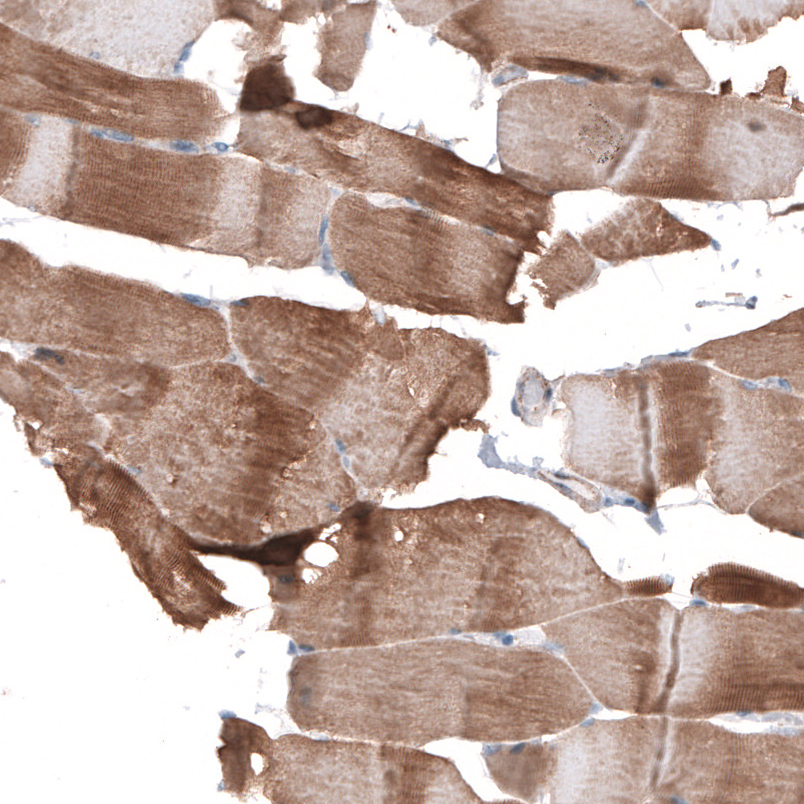

Immunohistochemical staining of human kidney shows strong membranous positivity in cells in glomeruli.